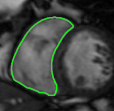

The problem above is a generalization of Horn & Schunck optical flow. Note that solving for the Horn & Schunck optical flow within each region separately does not lead to motions such that at the interface, they have equal normal components (see Figure 1), whereas the solution of (5) to be presented in subsequent sections does. Note that computing Horn & Schunck optical flow in each region requires boundary conditions (and typically they are chosen to be Neumann boundary conditions: and on ). Note that replacing these boundary conditions with the boundary constraint (6) does not specify a unique solution. Also, while Horn & Schunck optical flow computed on the whole domain naturally gives a globally smooth motion, which by default satisfies matching normals at the interface, this is not natural for the ventricles / myocardium, where different motions exist in the regions (see Figure 2), and the motions should not be smoothed across the regions.

![]() |

| image + boundary | next image | within region optical flow | our method |